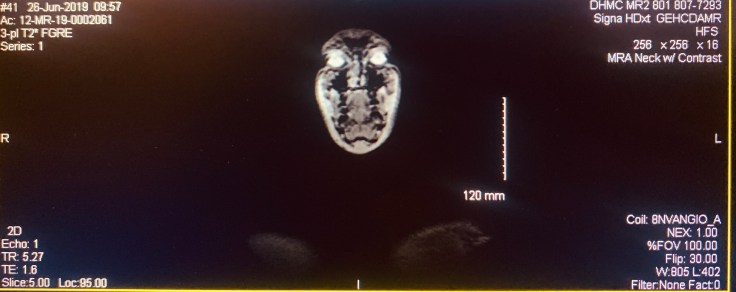

I got my MRI and MRA images yesterday and today and it’s super wild to be able to dissect myself, reverse and repeat. It’s not everyday you get to see your brain structures, musculature, nerve pathways, and to watch your blood flow in real-time. It’d be even more fascinating if it wasn’t so frustrating. The analysis still needs to be done on the MRA but the MRI came back hard-normal. If the MRA comes back ok I don’t even know where we go from here.

Living in the future is pretty wild. I literally had my MRA done this morning and came home with motion images of the results. Thinking about how the whole thing works it almost seems like fiction. You excite some atoms, create a magnetic field, and then interpolate the resulting radio frequency scan. Put that all together and you can see differentiated structures and functions.